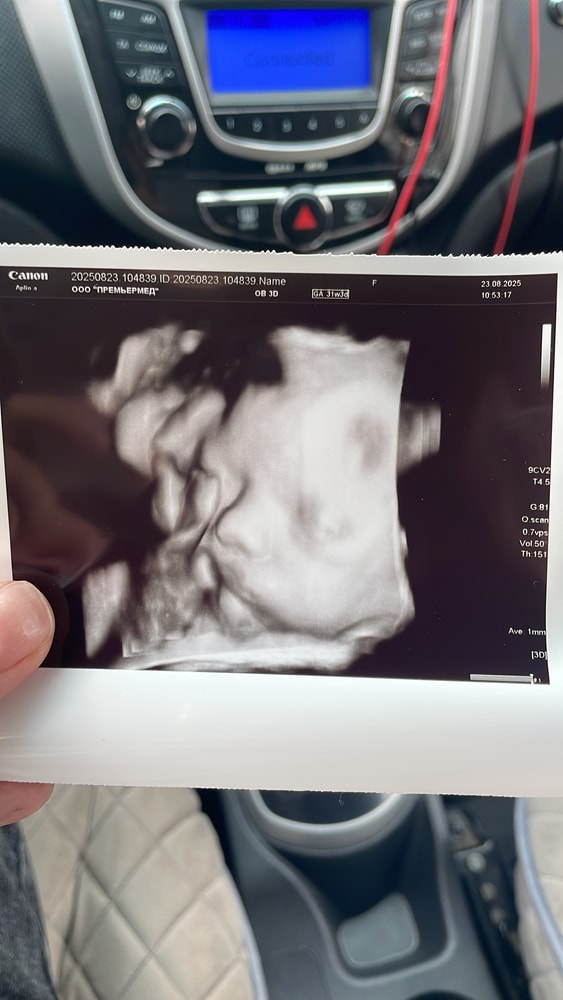

Марина ,

Вот нос нормальный ,на 32 неделе 3д узи делала даже. Нипт я тоже сдавала. Я почему-то испугалась делать прокол.